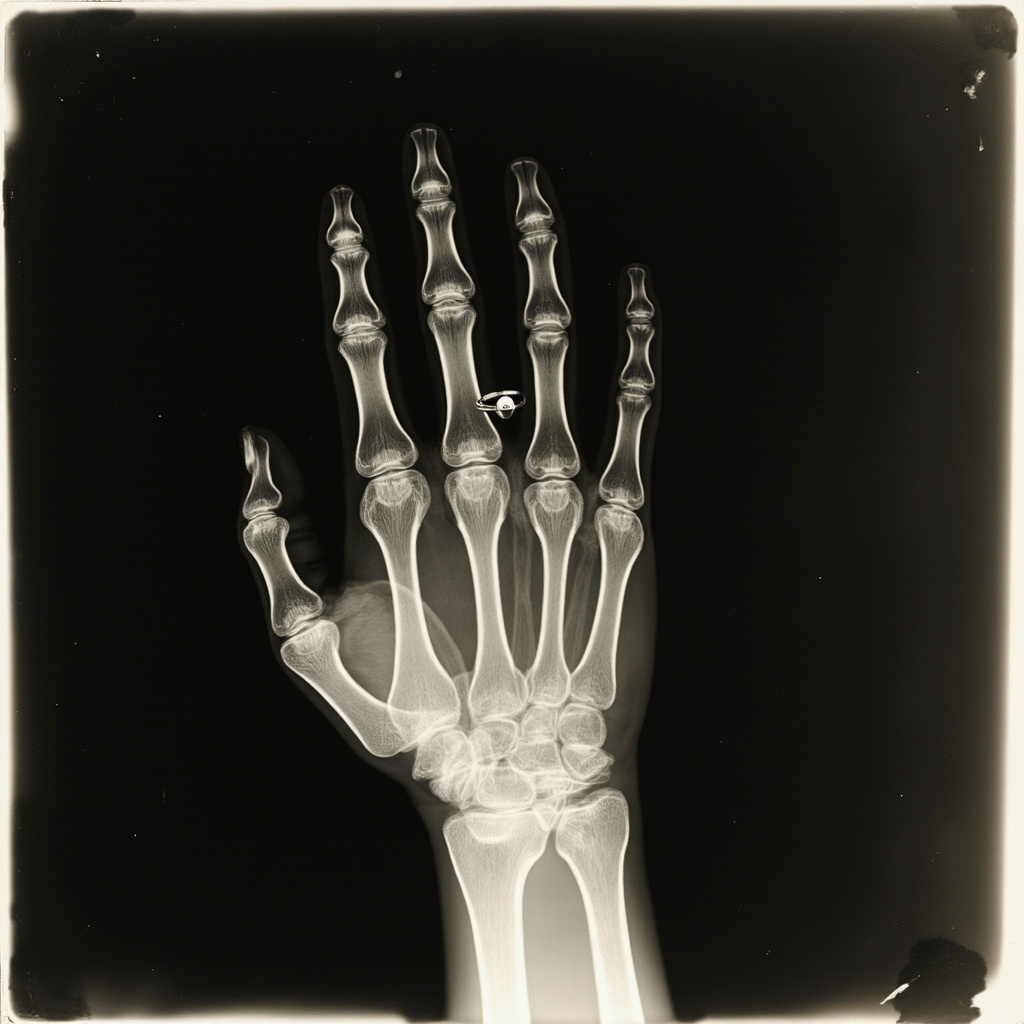

On December 22, 1895, Röntgen asked his wife Anna Bertha to place her hand on a photographic plate while he aimed his X-ray tube at it. The exposure took about 15 minutes — during which Anna Bertha had to hold perfectly still. The resulting image was haunting: the dark shadows of her bones clearly visible, her wedding ring floating ghostlike around her finger. When she saw the image, she reportedly gasped, “I have seen my death.”

Röntgen published his findings on December 28, 1895, and the news exploded across the globe with a speed that rivaled the telegraph itself. Within days, newspapers on every continent were breathlessly reporting on the “new photography” that could see through flesh to the bones beneath. The public was equal parts fascinated and terrified.